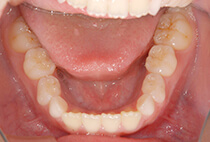

5歳6ヶ月、受け口が気になり、お母様と一緒にご来院。

「幼稚園の間に治療スタートしたい」「小学校入学時には装置に慣れた状態でいたい」とのご希望で、矯正治療をスタートしました。

治療は、急速拡大+前方牽引装置から。

1ヶ月で骨格バランスが大きく改善しました。

小学1年生の7ヶ月後には、さらにバランスの整った噛み合わせに。

成長に合わせて3回の急速拡大を行い、夜間のマウスピースとお口の機能訓練で成長をサポート。

小学生を正常なバランスで過ごすことができました。

中学校入学と同時にマウスピースを卒業し、今後は予防管理へ移行予定です。

「早めに始めてよかった」と喜んでいらっしゃいます。